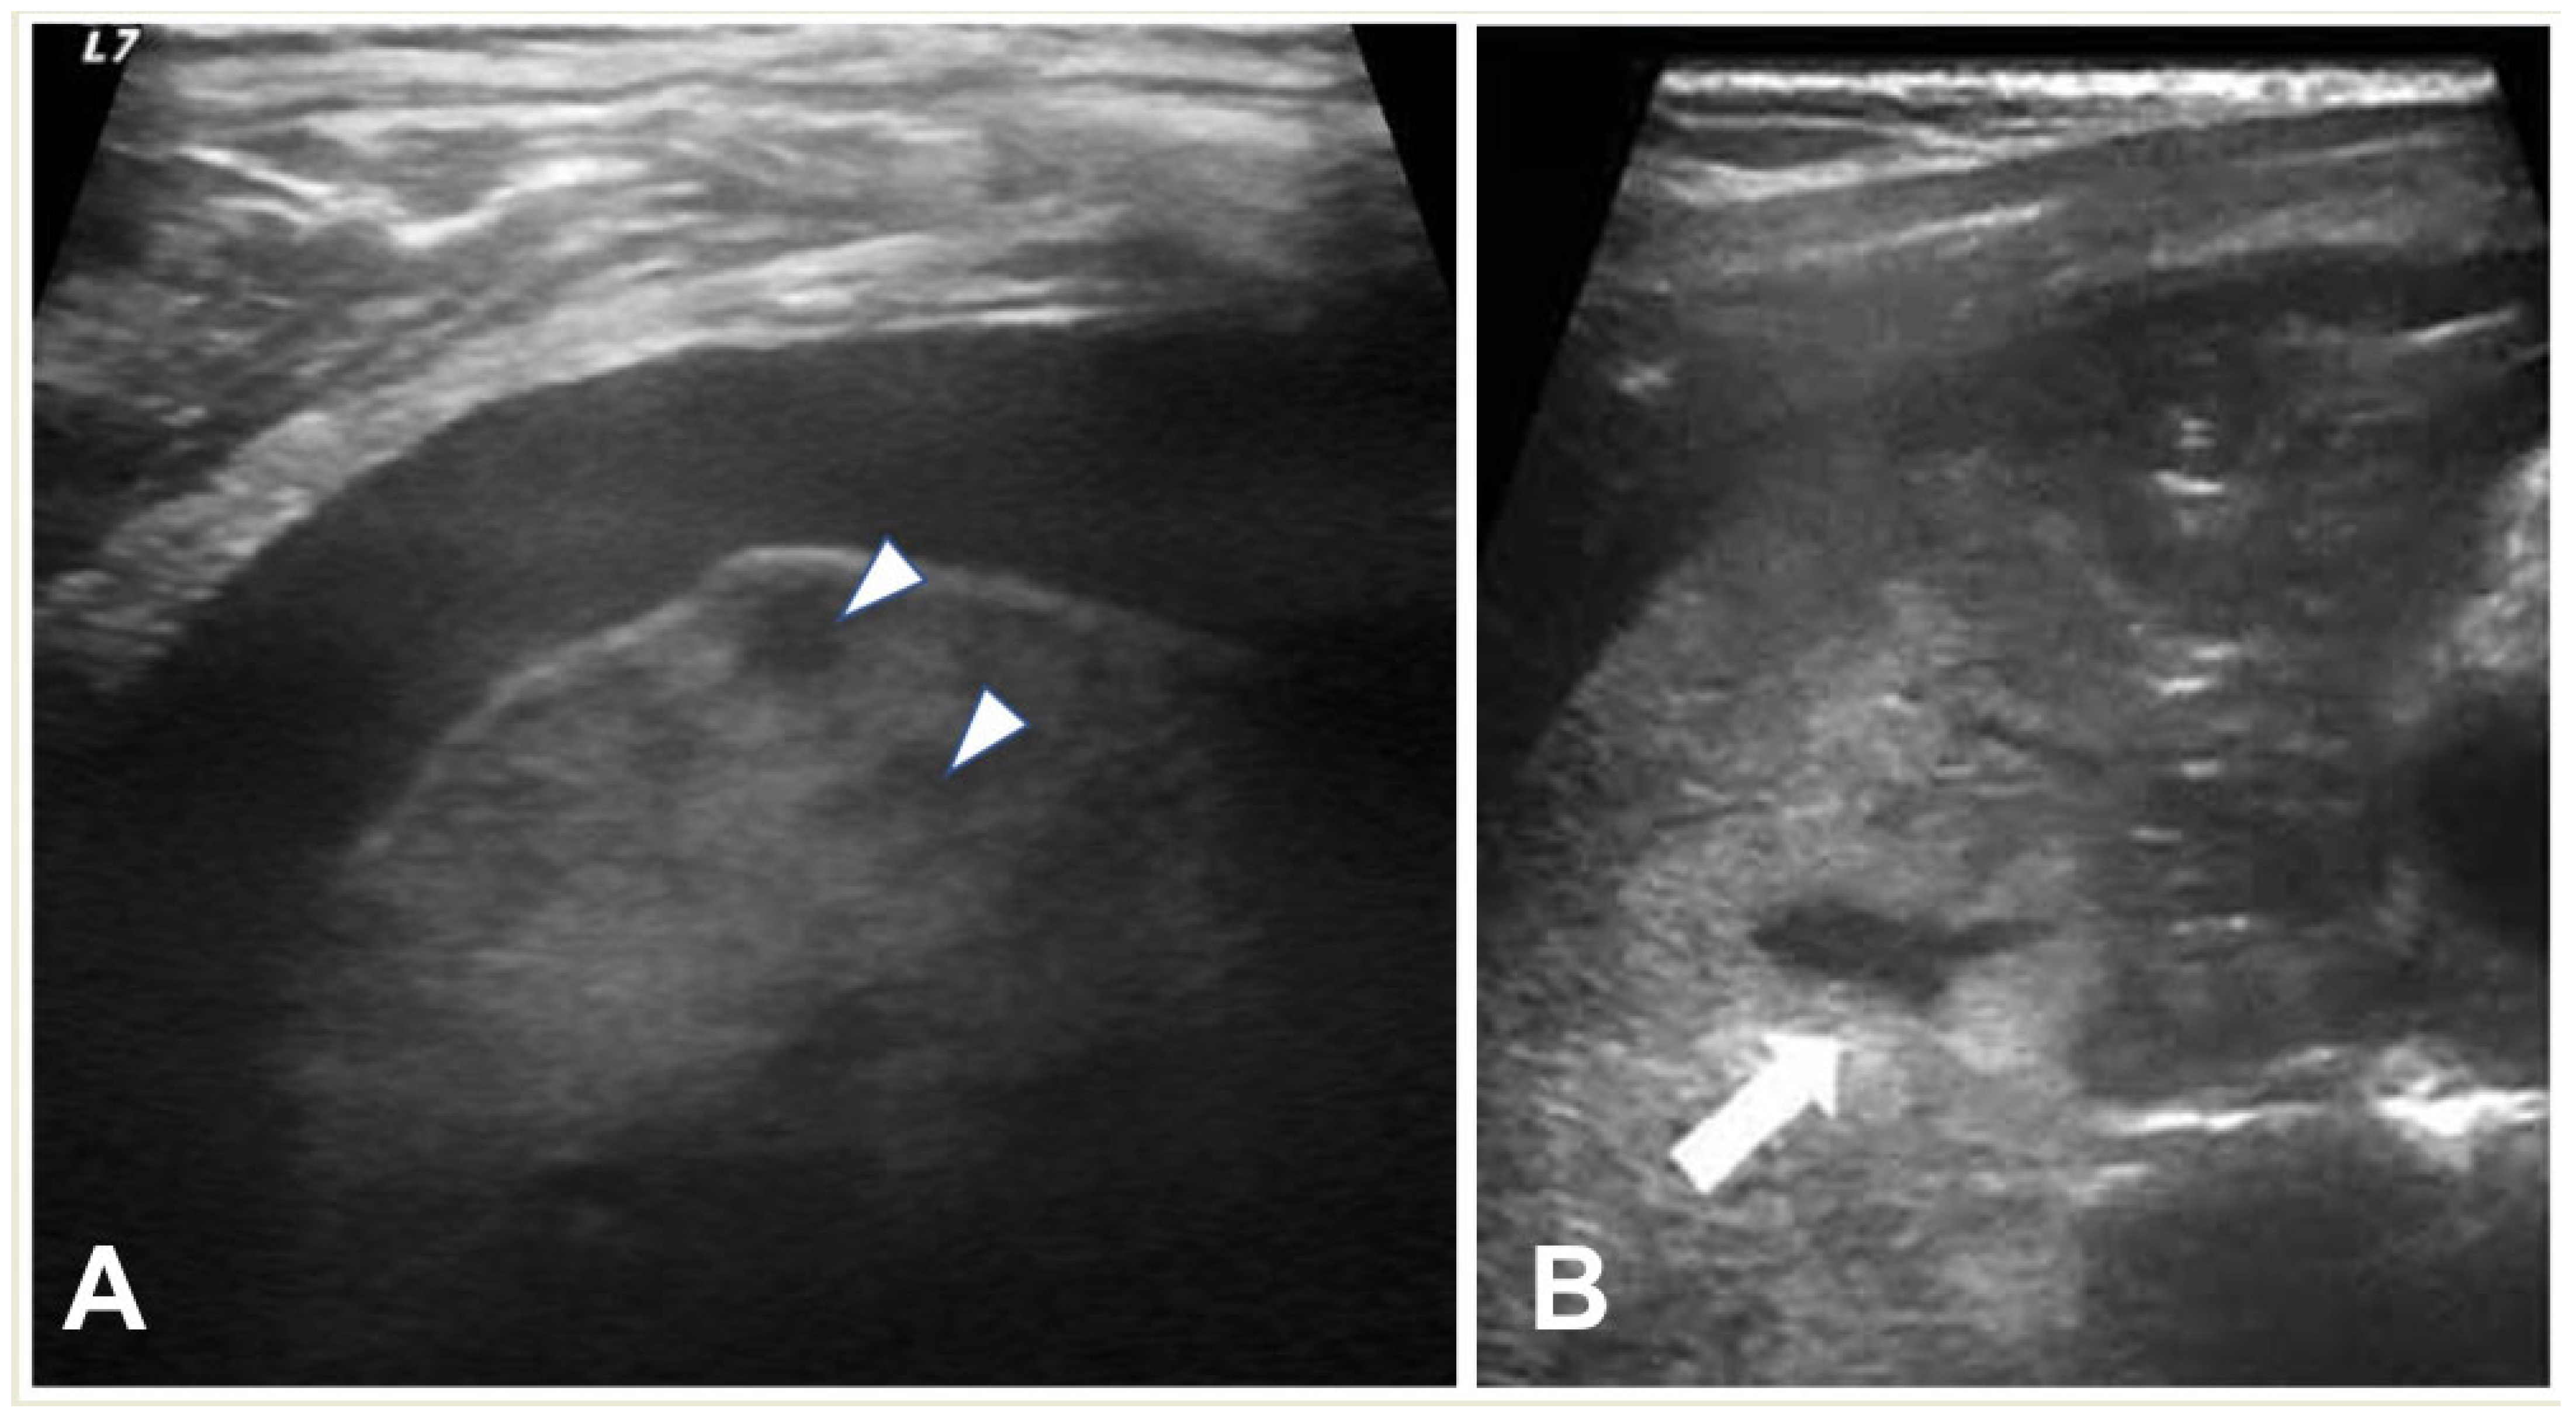

2.4.1. Pleural Effusion—Empyema

2.2. Lung Ultrasound